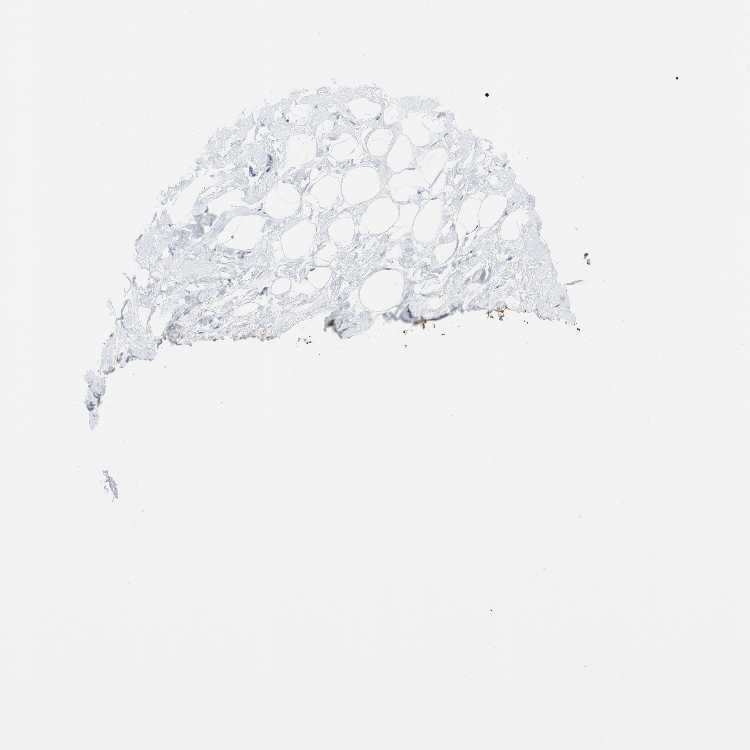

BREAST - Antibody stainingi

Antibody staining in the annotated cell types in the current human tissue is reported as not detected, low, medium, or high, based on conventional immunohistochemistry profiling in selected tissues. This score is based on the combination of the staining intensity and fraction of stained cells.

Each image is clickable and will lead to virtual microscopy that enables deeper exploration of all samples and also displays staining intensity scores, fraction scores and subcellular localization as well as patient and tissue information for each sample.

Antibody HPA005899Antibody HPA005914

Adipocytes Not detectedNot detected

Glandular cells LowLow

Myoepithelial cells LowNot detected